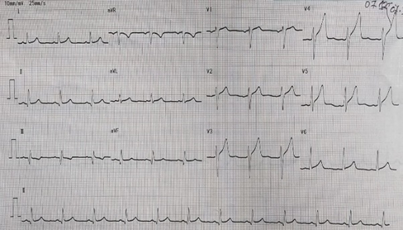

He had history of diabetes mellitus, systemic arterial hypertension, bronchial asthma, and skin allergy. He was non-smoker, non-alcoholic and had no history of similar diseases and genetic disorders but had history of coronary artery disease in his family. On physical examination, pulse rate was 88 beats/min, blood pressure was 120/80 mmhg, respiratory rate was 22/min, SpO2 was 97% on room air. Electrocardiogram (ECG) showed Old MI(Inferior).